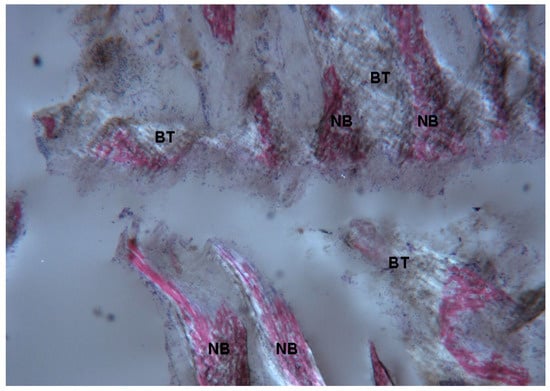

2.1. Histological Results

2.1.2. Test 7-Days (Subject 1, Female)

2.1.3. Test at 30 Days (Subject 2, Male)